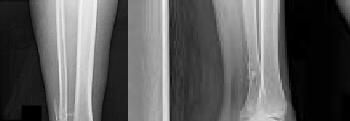

A 40-year-old pedestrian is struck by a vehicle and sustains a complex proximal tibia fracture. Imaging confirms a Schatzker Type IV fracture involving the medial tibial plateau. What is the typical mechanism of injury for this specific fracture pattern, and which anatomic structure is placed under the highest tensile stress?

A Schatzker Type IV fracture involves a fracture of the medial tibial plateau. Unlike lateral plateau fractures (which are typically low-energy valgus injuries), a medial plateau fracture usually results from a high-energy varus force combined with an axial load. This mechanism places extreme tension on the lateral-sided structures, frequently leading to associated Lateral Collateral Ligament (LCL), posterolateral corner, and/or peroneal nerve injuries.